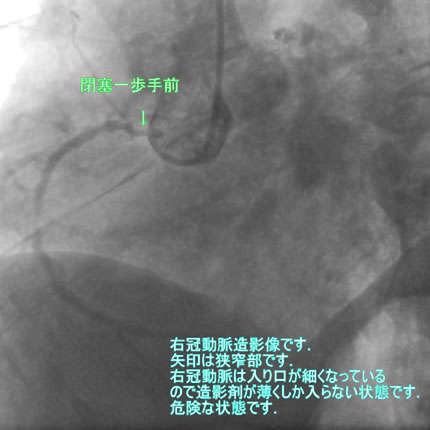

図1-1 右冠動脈造影

よく解らないと思いますが、冠動脈に多数の狭窄があることと冠動脈が「こぶ状変化(医学用語で瘤状変化)」を生じているのが解ると思います。